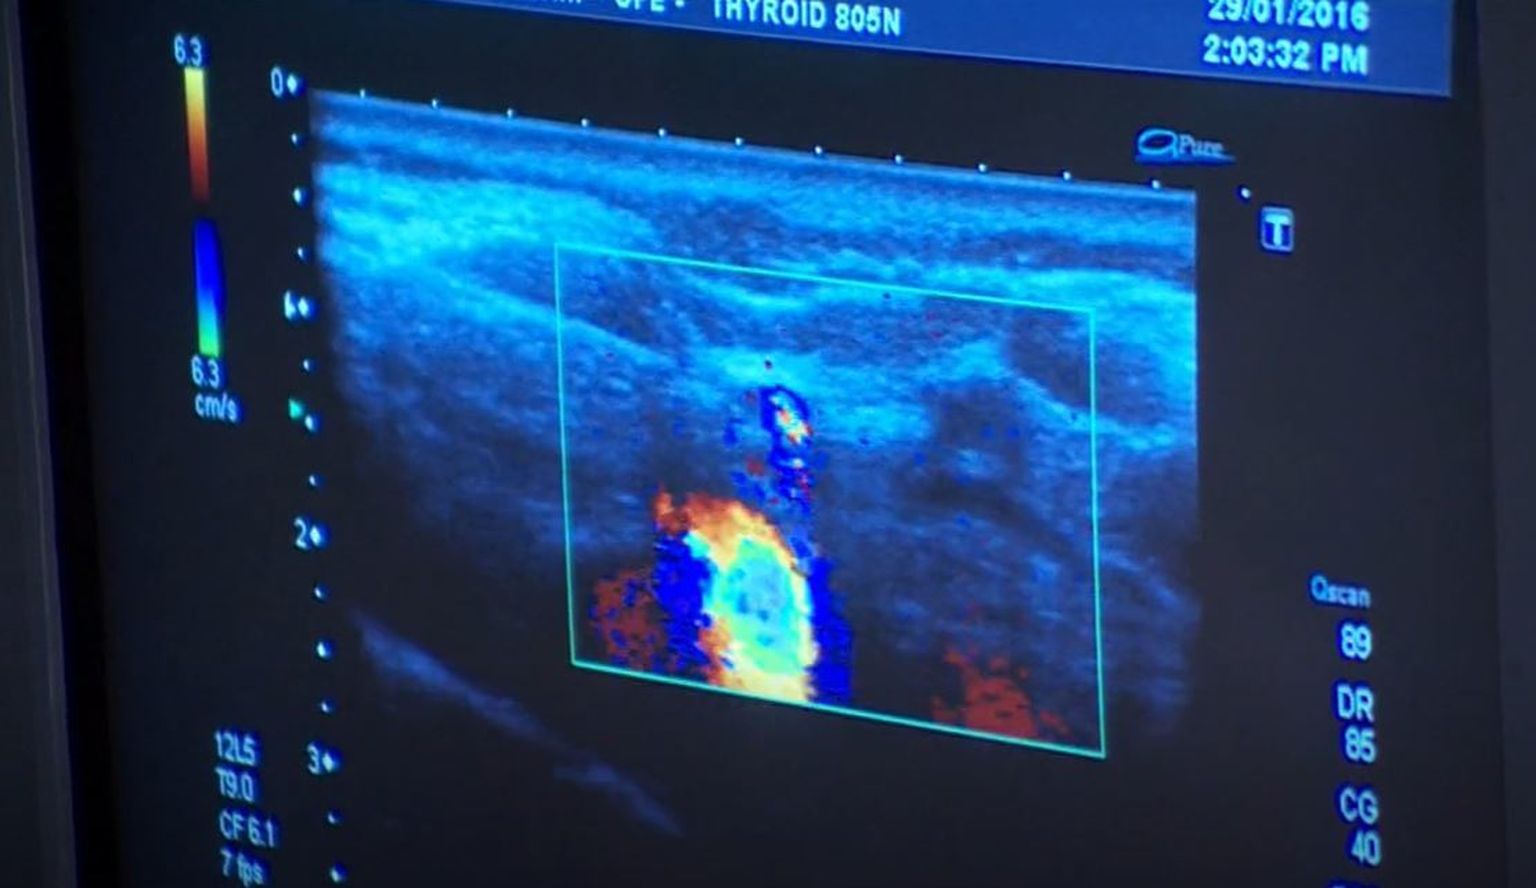

• Karcinomi glave i vrata - 4 Foto: DNEVNIK.hr

• Karcinomi glave i vrata - 3 Foto: DNEVNIK.hr

• Karcinomi glave i vrata - 2 Foto: DNEVNIK.hr

• Karcinomi glave i vrata - 1 Foto: DNEVNIK.hr